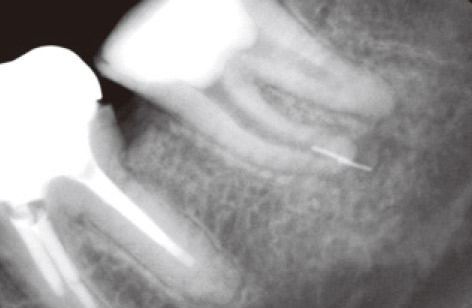

左下7番の近心根にUファイルを折れ込んでしまったそうです。患者さんは30歳の女性で、自発痛で苦しんでいました。デンタルでは破折ファイルが2本重なっているように見えます(図4)。

図4 治療時に近心根に折れ込んでしまったファイルの除去を依頼された。下顎左下第二大臼歯の術前デンタルX線写真。近心根根尖部にファイルが2本重なってみえる。自発痛が続いていた。

図6 かなりの時間を要し、1本目のファイルを除去した。除去後のデンタルX線写真。エンド三角が切削され、近心根管はストレート化されている。